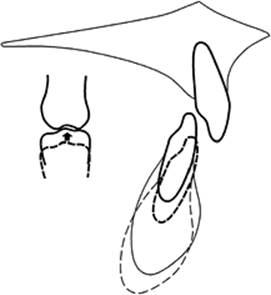

A reduced lower facial height is associated with a forward rotational pattern of growth. This usually means that the mandible becomes more prognathic with growth (Fig. 10.2). While this pattern of growth is helpful in reducing the severity of a Class II skeletal pattern, it also has the effect of increasing overbite unless an occlusal stop is created by treatment to limit further eruption of the lower incisors and to shift the axis of growth rotation to the lower incisal edges.

Fig. 10.2. Diagram showing how, despite a forward pattern of facial growth, the overbite can become worse in an untreated Class II division 2 incisor relationship.